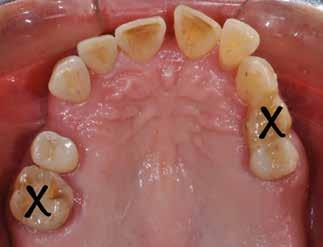

Patienttilfælde 1 (Fig. 1) er en 37-årig kvinde, henvist efter succesfuld behandling af stadie 3-parodontitis. Der er nu sundt

Før behandling

parodontium, ingen pocher over 4 mm, og både blødnings- og plakindeks er under 10 %. Patienten er motiveret for ortodontisk behandling, da hendes tænder er vandret over tid, delvist som følge af reduceret parodontium.

Der ses anterior trangstilling i begge kæber og overerupterede 1+1 og 2,1-1,2, hvilket resulterer i dybt bid med 2- tæt på ganepåbidning. Der er normale sidetandsrelationer, men der ses 5 mm horisontalt overbid (HOB) og 7 mm vertikalt

overbid (VOB). Papillen mellem 1+1 er betydeligt reduceret pga. fæstetab, og de mesialt kippede 1+1 har resulteret i en ”dark triangle”. Den facioorale funktion er for nuværende i.a. Panoramarøntgen (Fig. 1, I) viser marginalt knogletab i begge kæber og fravær af 8,7+7,8 og 8,7-8.

Der planlægges alignerbehandling af begge kæber med intrusion af 1+1 og 2,1-1,2, nivellering af trangstilling UK med interproksimal reduktion (IPR) (Fig. 2 A, B) og senere IPR OK for reduktion af dark triangles mellem incisiverne efter nivellering. Patienten instrueres i at benytte alignere 20-22 timer/ dag med alignerskift hver 7. dag, og patienten ses hver 3.-8. uge under forløbet. Den første alignerserie består af 16 alignere for nivellering OK/UK og IPR i UK (Fig. 2). Efter denne serie planlægges IPR mellem incisiverne i OK for reduktion af dark triangles (Fig. 3) samt yderligere intrusion af OK og UK-fronten i 12 refinement-alignere. Patienten udviser god kooperation og er meget tilfreds med alignerapparaturet, som er mindre synligt end det faste apparatur (Fig. 4).